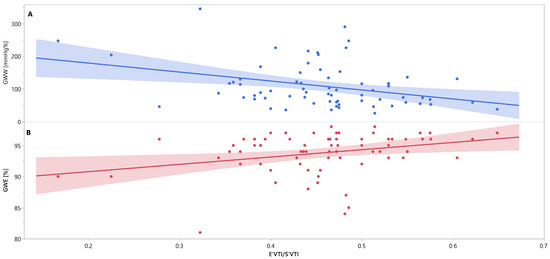

Mutual associations between PSD, GWW, GWE, IVRT and E′VTI/S′VTI are additionally shown in Figure 3, Figure 4 and Figure 5 as linear regressions.

Figure 5.

Linear regression lines for associations between E′VTI/S′VTI and GWW (panel A, line and points in blue), and GWE (panel B, line and points in red) in healthy people. Abbreviations: E′VTI/S′VTI—systolic–diastolic coupling, GWW—global wasted work, GWE—global work efficiency.